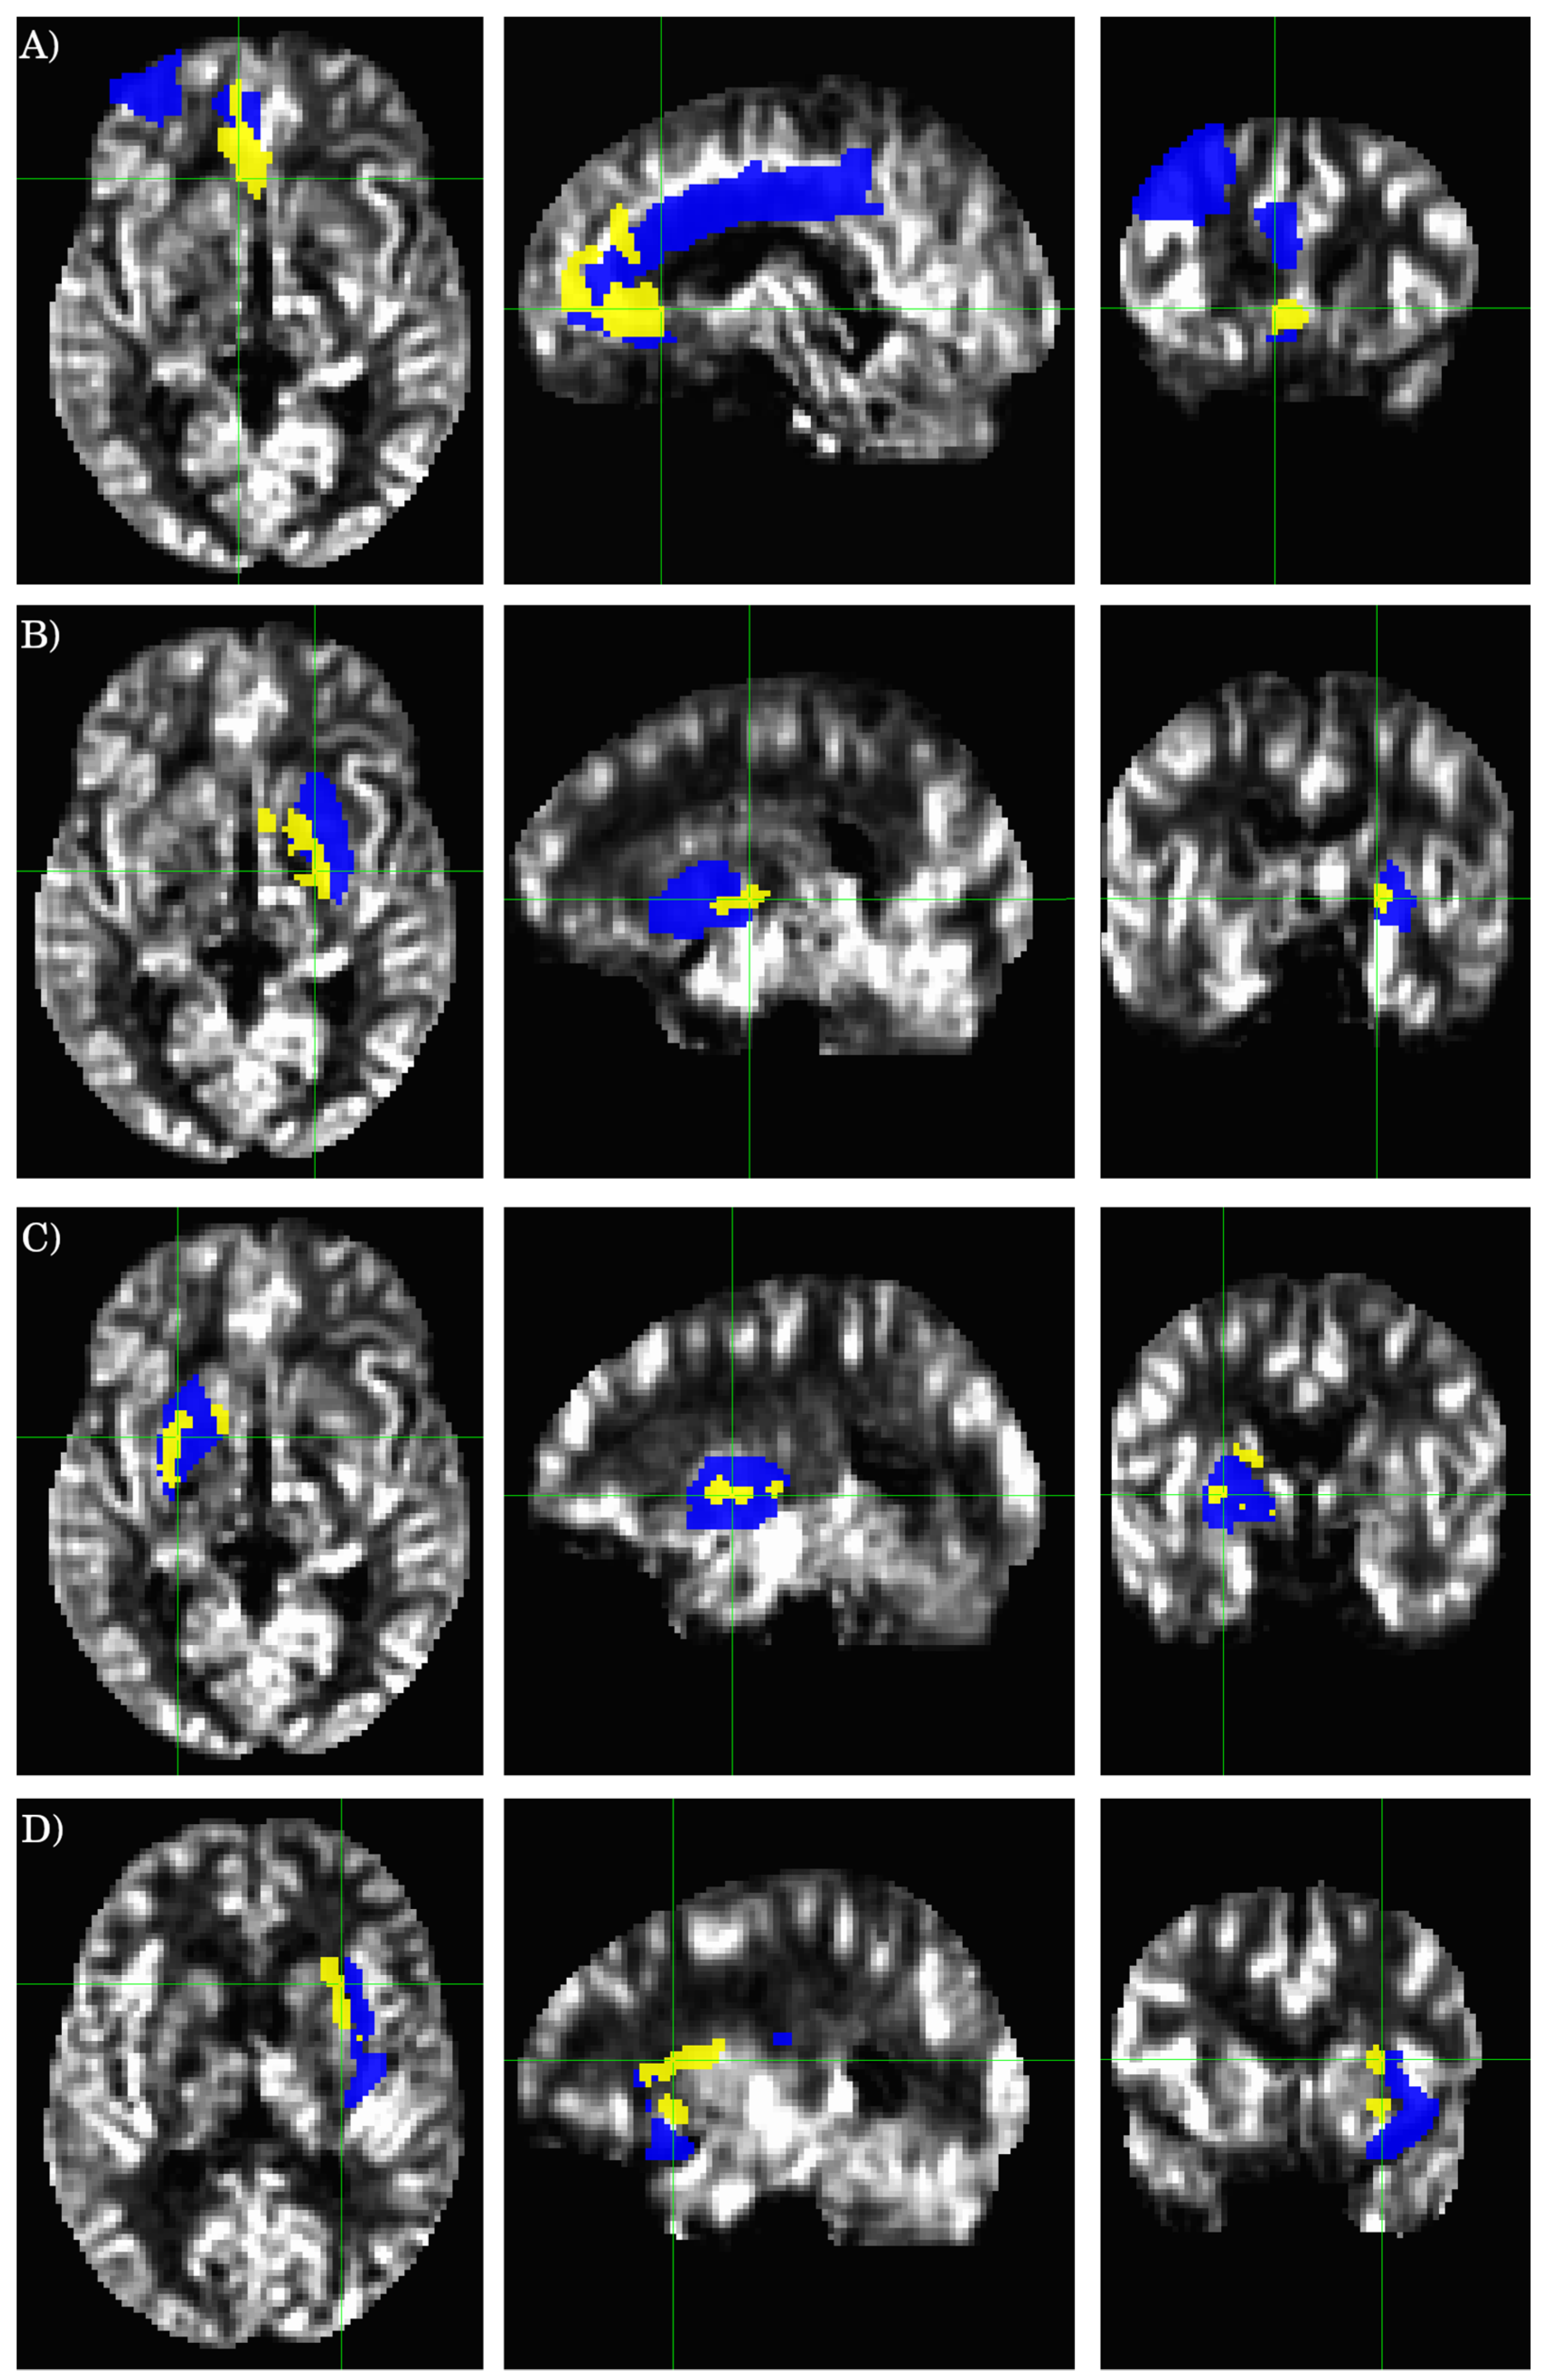

The results for the AAL ROI-based analysis are summarized in Table 3, and Figure 2 and Figure 3. There is an overall good agreement between the ROI-based analysis and the data-driven voxel-wise analysis. However, the clusters detected by the voxel-wise analysis do not coincide precisely with the atlas-based ROI definition. A cluster can partially overlap with multiple AAL ROIs. AS illustrated in Figure 3A, the largest cluster detected by the voxel-wise analysis (ROI 1 in Table 2), partially overlaps with three different AAL ROIs (AAL ROIs 7, 31, and 33, see Table 3), including the left middle frontal gyrus (AAL ROI 7), the left anterior cingulate (AAL ROI 31), and the left middle cingulate (AAL ROI 33). Similarly, ROI 2 (see Table 2 and Figure 3B) detected by the voxel-wise analysis partially overlaps with the left putamen (AAL ROI 73) and pallidum (AAL ROI 75). ROI 3 (see Table 2 and Figure 3C) detected by the voxel-wise analysis partially overlaps with the right putamen (AAL ROI 74) and pallidum (AAL ROI 76).

Figure 3.

Cross-sectional display of the relevant AAL ROIs and statistically significant clusters as detected by the voxel-wise two-sample t-test. The background image is the average rCBF result from the healthy controls. The yellow-colored regions show the clusters detected by the voxel-wise two-sample t-test, and the blue-colored regions depict the overlapping AAL ROIs. The crossing green lines indicate the locations of the cross-sections. (A–D) correspond to the ROIs 1-4 defined in Table 2, respectively.

There are also notable differences in the results obtained from the voxel-wise and ROI-based analyses. ROI 4 (see Table 2 and Figure 3D) detected by the voxel-wise analysis partially overlaps with the left insula cortex (AAL ROI 29); however, the ROI averaged rCBF values between HC and ME/CFS patients are not significantly different for the entire AAL ROI 29, as assessed by the ROI-based analysis (see Table 3). On the other hand, the voxel-based analysis did not detect any significant cluster in the regions defined by AAL ROIs 43 (L calcarine) and 47 (L lingual gyrus), as expected from the ROI-based analysis results (Table 3).